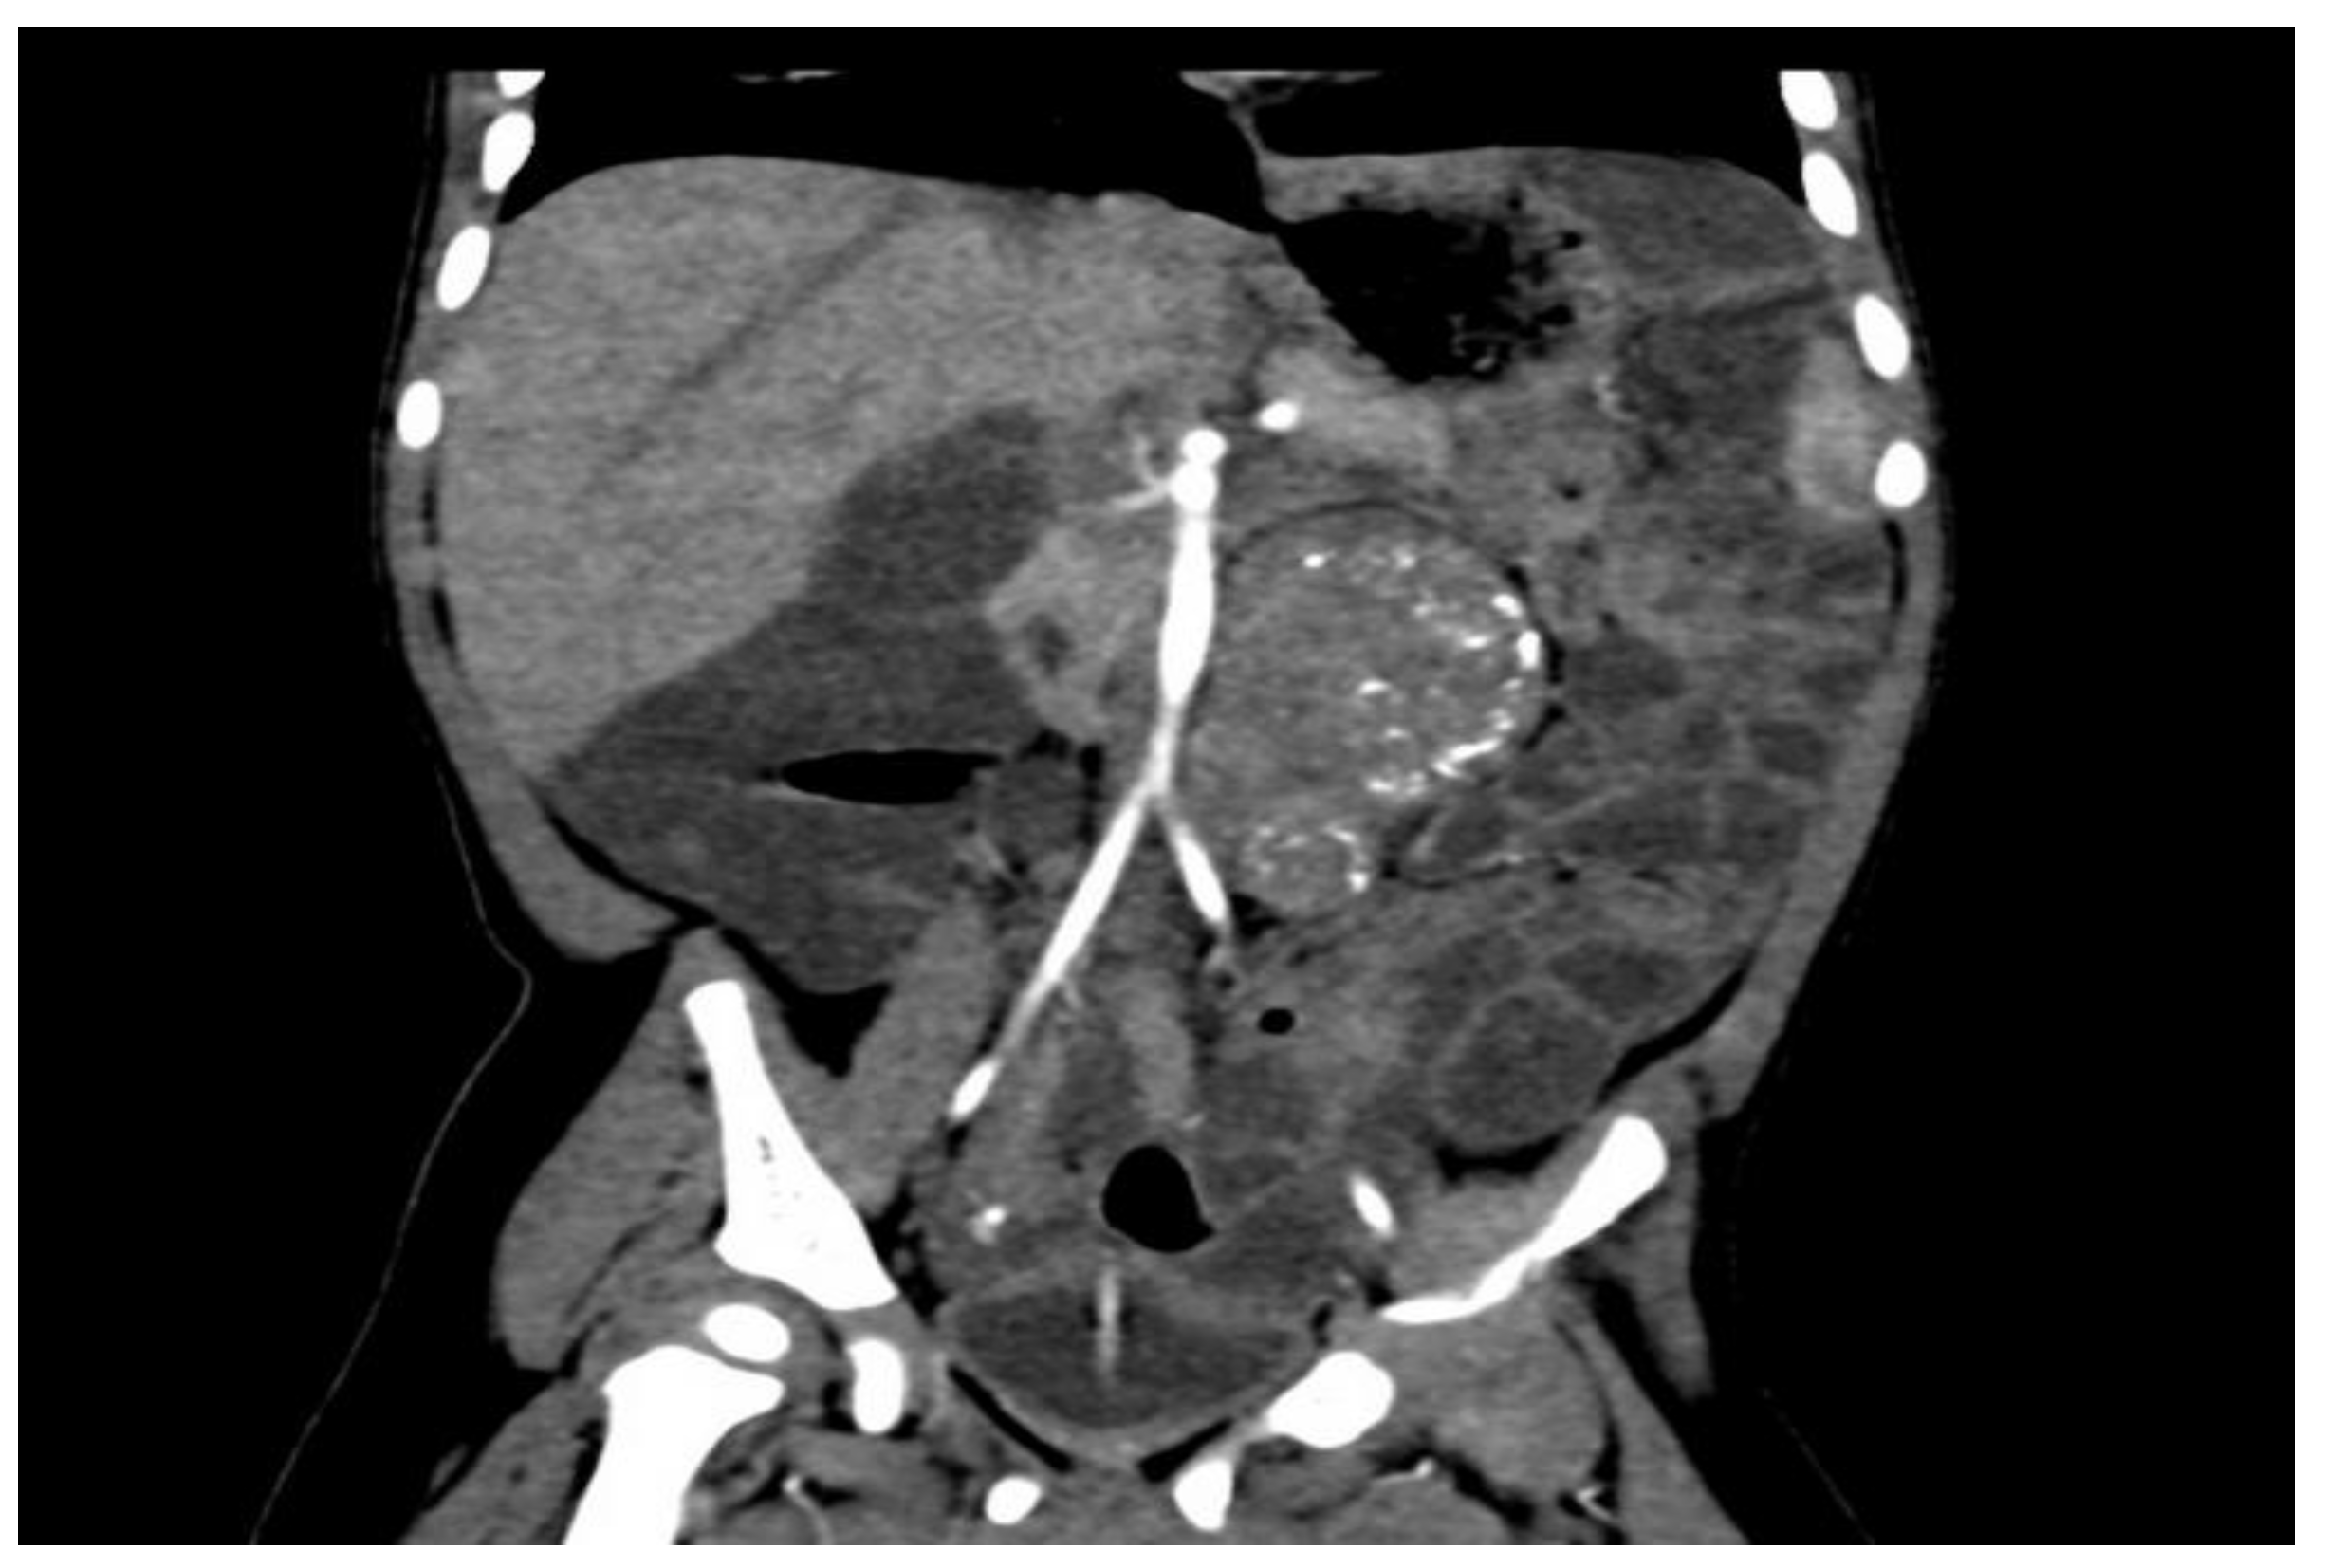

Following an abdominal computed tomography (CT) scan, an abdominal ultrasound revealed a calcified mass approximately 6/4 cm in diameter anterior to the L1–L4 lumbar spine and aorta but not in contact with the left kidney. There were no anomalies in the pancreas (Figure 2).

Figure 2.

Retroperitoneal tumor with calcifications, as shown on a CT scan.